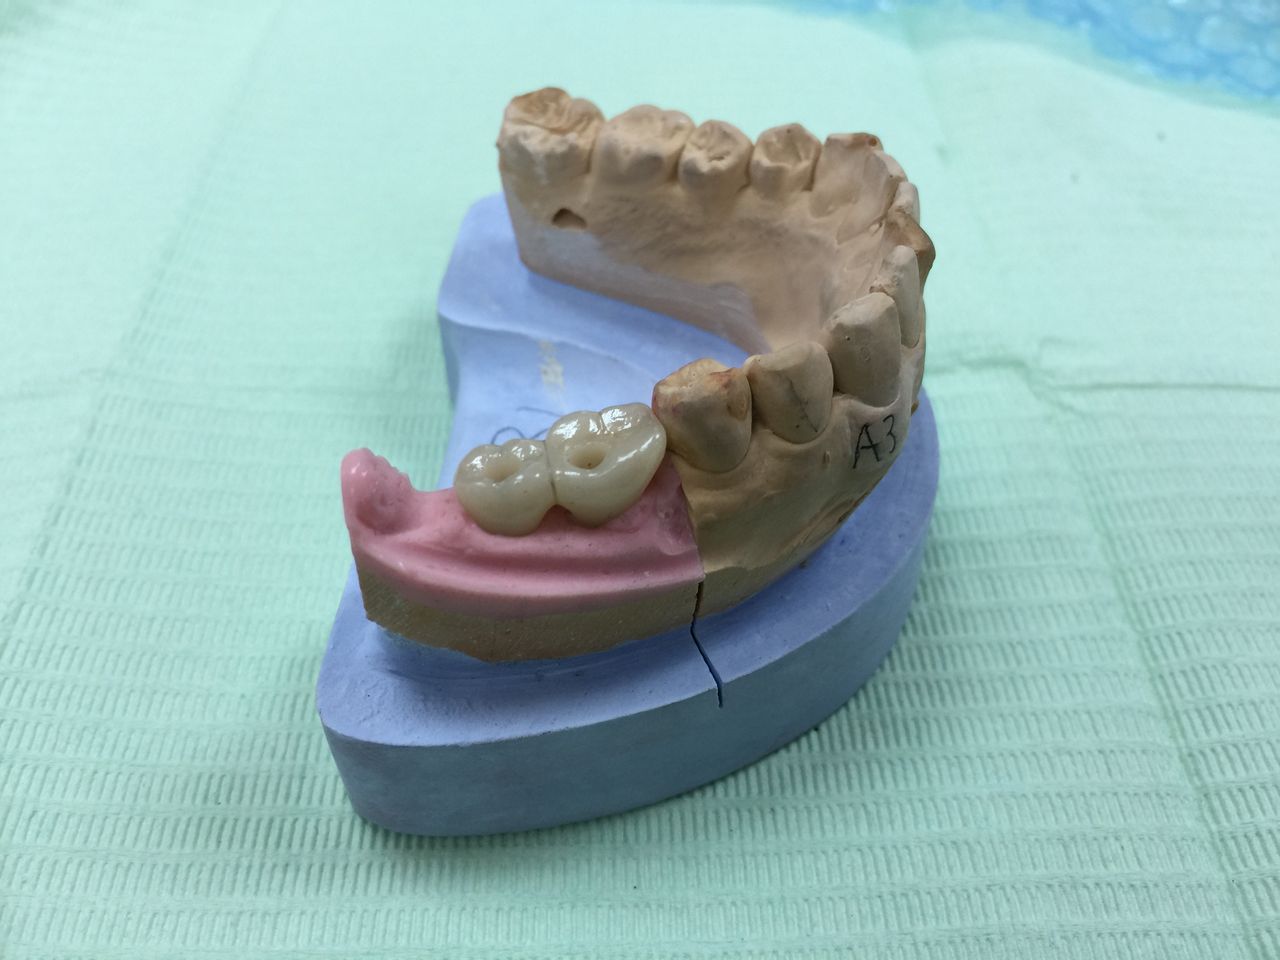

先日インプラントの型取をした患者さんの被せ物が出来上がってきました。

技工士さんが、コレをもとに全てがセラミックでできた被せ物を作ってくれます。